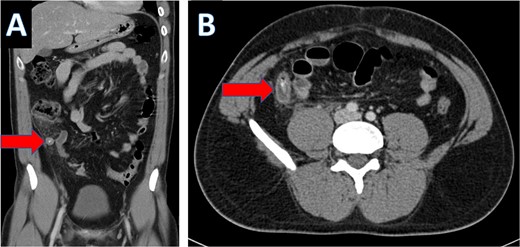

An IV contrast-enhanced CT scan of the abdomen and pelvis revealed an 8-mm proximal to mid-ureteral obstructive stone on the right side (Fig. 1), causing severe hydronephrosis of the right kidney and proximal hydroureter (Fig. 2).

CT scan showing hydronephrosis of the right kidney (A: coronal; B: axial).